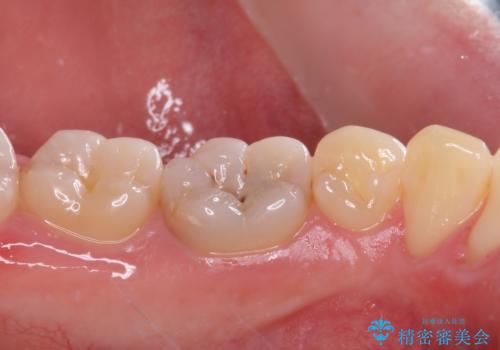

神経近くにまで及んだ大きなむし歯のセラミッククラウン

- 下顎左右奥歯に虫歯で痛みを感じるとのことで来院された患者様です。

むし歯が大きく、神経を取り除く可能性があることを理解いただいた上で虫歯を取り除き、その後はオールセラミッククラウンにて補綴することとしました。

虫歯除去後に痛みは収まり、神経も保存することができました。

変色していた歯もセラミッククラウンで自然な色合いとなり、患者様には大変満足していただきました。